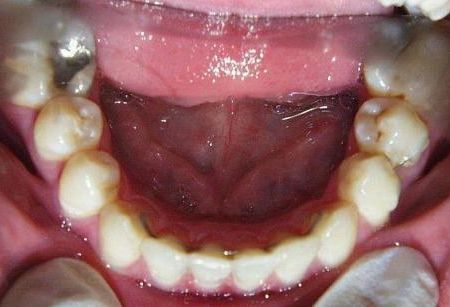

Vor der Behandlung